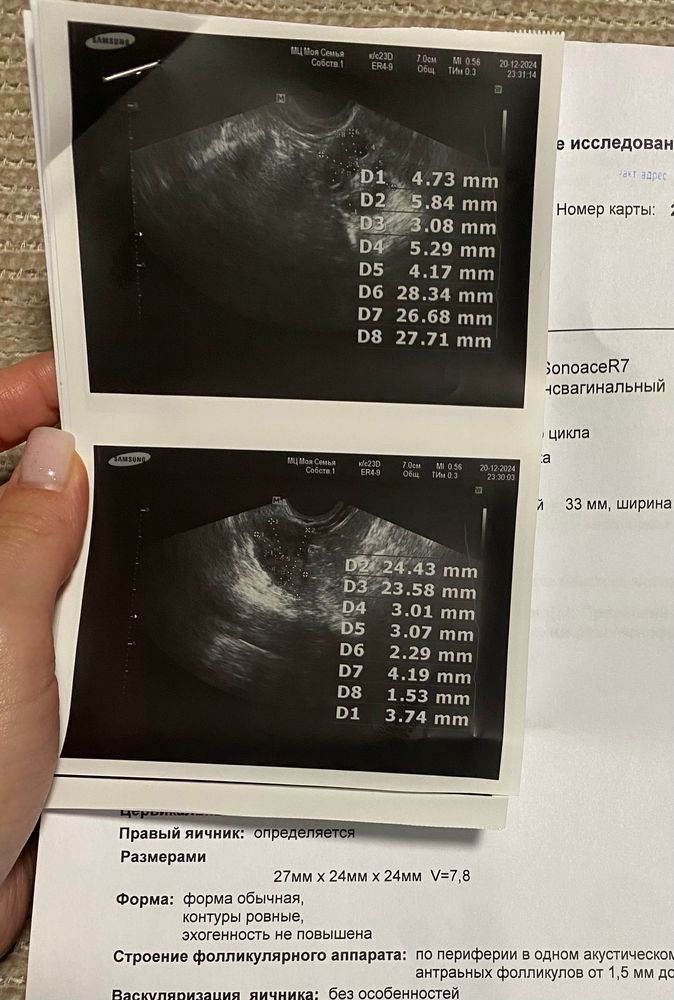

Ждем дня Х (Признаки беременности / Тесты)Всем добрый день, такой вопрос. Цикл посл год был относительно регулярный 30-34 дня. До этого иногда были задержки сильные. Начали планировать Б в октябре, но там уже скорее всего пропустили О, потому что ПА были за неделю до М. Прошлые месячные (в ноябре) пришли ровно по часам. После них начала отсл О тестами. Так и не поймала, но ПА были регулярные. Потом задержка, тесты отрич, к Гине пошла, ХГЧ отриц. На 18 день задержки пошла на УЗИ. Там сказали, что цикла вообще нет.. МФЯ и эндик 5,3 мм. Сами М придут неизвестно когда, можно вызвать Дюфастоном или подождать. Я решила подождать ещё пару недель и после НГ если не придут , начать Дюфастон. И после этого сдать на гормоны в начале цикла.

В общем вопрос в том, что правильно ли я поняла, что этот цикл (до того как начнутся месячные) точно пролетный? Можно расслабится? По картине УЗИ же точно О уже не будет?